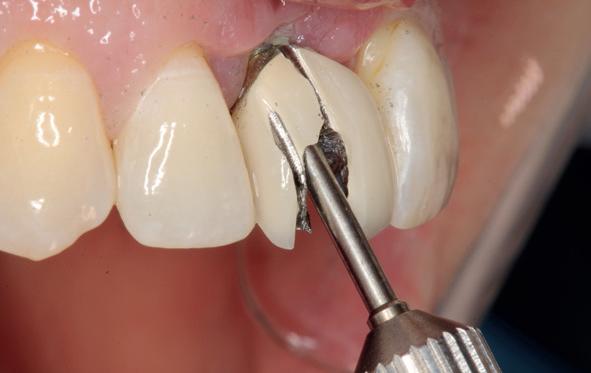

Deze casus beschrijft een uitgebreide immediate implantaatbehandeling bij een patiënt die door meerdere collega’s werd geweigerd. Niet omdat de mogelijkheden ontbraken, maar omdat de complexiteit vroeg om een perfect afgestemde samenwerking. Het verhaal laat zien hoe de assistent in zo’n traject veel meer is dan een uitvoerende kracht of “mal”, maar een dynamische surgical guide die het proces mede stuurt, bewaakt en mogelijk maakt.De patiënt: wanneer alles samenkomt

Ze kwam binnen op een dinsdagochtend, iets voor achten. Een vrouw van begin zeventig, met een zachte stem en ogen die meer vertelden dan haar woorden. Ze vertelde dat ze een eigen B&B had en dat ze zich nauwelijks kon voorstellen gasten te ontvangen zonder tanden. Op dit moment kon ze echter nauwelijks lachen. “Het doet pijn… en het ruikt soms ook niet goed,” zei ze bijna verontschuldigend. Haar oude bovenbrug, die ze al meer dan twintig jaar droeg, was langzaam maar zeker ingestort. Er was sprake van cariës onder meerdere pijlers, pusafvloed,

chronische ontsteking en een brug die mobiel was en elke beet pijnlijk maakte. Ze had inmiddels meerdere tandartsen bezocht. Drie hadden haar geweigerd. Te complex. Te veel wensen. Te onvoorspelbaar.

De kern van haar vraag was eenvoudig en tegelijkertijd uitdagend: Is het mogelijk om mijn huidige brug te dupliceren en een nieuwe brug te vervaardigen met minder complicaties?